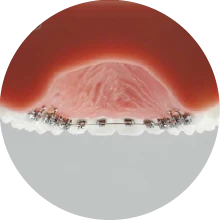

裏側に装置をつける矯正

歯の裏側に装置をつけるため、基本的に周囲から矯正装置は見えません。歯の裏側の形は表側に比べて、個人差が大きいので、装置をオーダーメイドで作製する必要があるため、コストが掛かります。その分、施術料が高くなってしまいます。

裏側に装置をつける矯正治療

上は裏側、下は表側に装置をつける矯正治療